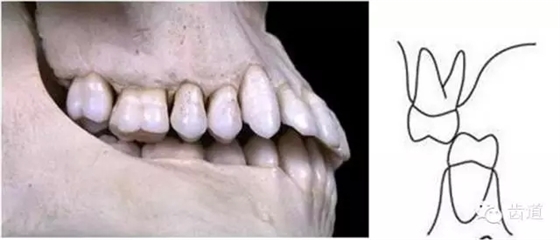

上下牙列間存在著覆蓋、覆牙合

覆蓋Overjet (the horizontal overlap)

覆牙合Overbite (the vertical overlap)

覆蓋(over jet,即超牙合):水平距離

覆牙合(over bite):垂直距離

覆牙合、覆蓋生理意義

a.保護(hù)唇頰舌軟組織

b.提高咀嚼效率